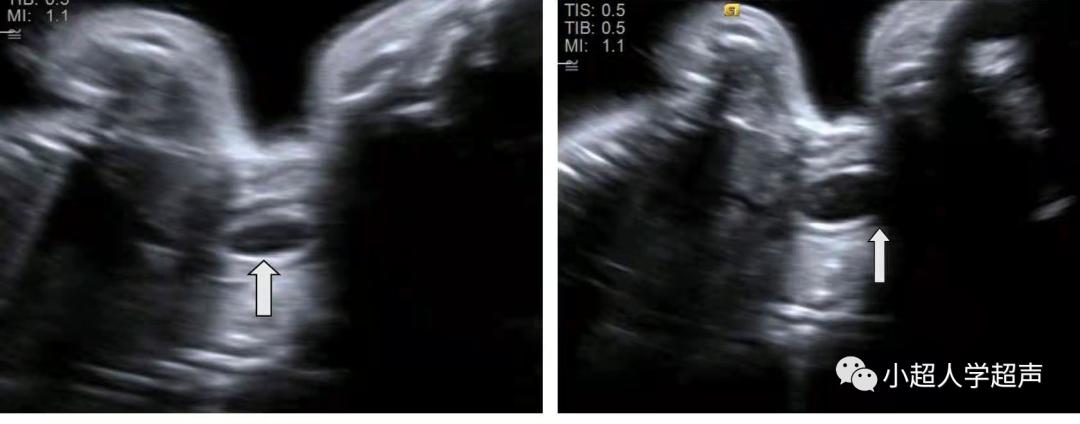

直接征象 :食道盲端的囊袋征,胎儿颈部的囊性结构

产前超声很难显示食管闭锁部位,所以很难进行准确的分型,常常通过羊水过多、胃泡不显示、腹围小等一些间接征象并动态观察胎儿吞咽羊水时是否出现颈部的“囊袋样”无回声来提示食管闭锁,因此产前超声对食管闭锁的检出率各家报道不一,大多不超过50%。

鉴别点:上述肿块在检查过程中形态、大小不变,有囊性肿块的占位效应。

食管闭锁的“囊袋样”无回声在检查过程中会观察到无回声结构 随胎儿吞咽动作大小有所改变 。